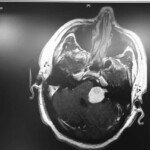

Sono partiti i lavori per una nuova sala operatoria ad alta tecnologia dedicata alla Neurochirurgia del San Filippo Neri.

Consideriamo questo un “premio” per la elevata produttività della nostra UOC, che nel 2015 ha effettuato oltre 250 interventi di chirurgia cranica, circa 200 dei quali in regime di elezione, in particolare:

– tumori intracranici benigni e non,

– chirurgia cerebrovascolare (aneurismi, angiomi, cavernomi),

– microdecompressioni vascolari in fossa cranica posteriore per nevralgia trigeminale e per torcicollo spastico.